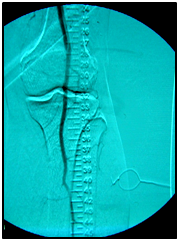

Endovascular procedure was done with antegrade access in the ipsilateral common femoral artery, diagnostic angiography confirmed: Patency of the femoral-popliteal axis, occlusion of the posterior and anterior tibial arteries, two critical stenotic lesions in the fibular artery and revascularization of the dorsalis pedis and plantar arteries by the fibular artery. To treat the fibular critical atherosclerotic lesions were performed a percutaneous transluminal angioplasty using a 0.0018in.guidewire, catheter support and a catheter balloon (3,0x6 mm and 3,5x 15mm).

Final angiographic control showed patency of the fibular artery and dorsalis pedis, with direct flow for the first metatarsal artery, thus guaranteeing enough flow to heal the ulcer in six months after the procedure. In conclusion endovascular treatment has a high technical eligibility with good reported outcomes and represents an alternative for diabetics with CLI Disease (Figure 1 and 2).

• Figure 2 From left to right showing percutaneous transluminal BTK balloon angioplasty, and revascularization of the dorsalis pedis and plantar arteries by the fibular artery.